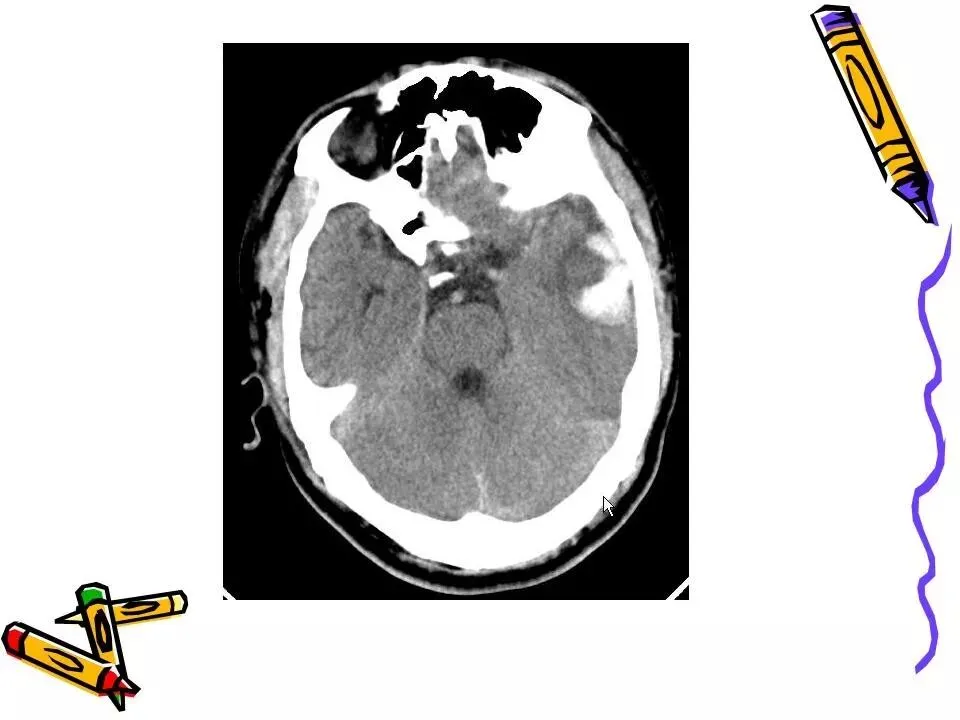

>常见颅脑外伤CT诊断(PPT)

常见颅脑外伤CT诊断(PPT)